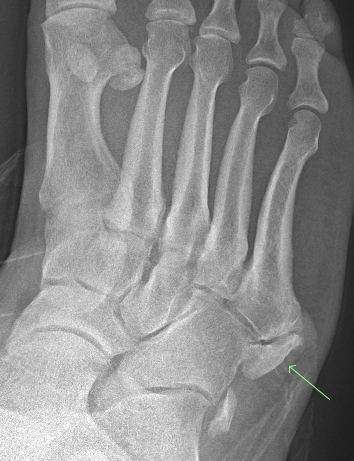

#CaseOfTheWeek‼️🥳‼️ ☢️🩻☠️Case#22☠️🩻☢️ #Mass 📲➡️➡️#Diagnosis❔❓❔ #FOAMRad #RadEd #MedEd #OrthoEd #OrthoTwitter @ssr_rwg @UWRadRes @ISSVA_org